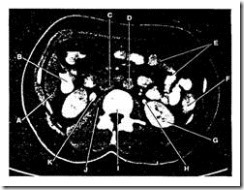

- Irisan Axial 5

Irisan axial 5 melihat bagian ke dua duodenum. Kepala pankreas terletak di luar dari duodenum. Jika bagian ke dua duodenum terlihat putih, maka dapat dikatakan tumor pankreas.

pemeriksaan radiology ct scan

Gambar 2.6 : Irisan Axial 5 (Bontrager, 2001)

Keterangan :

A. Lobus kanan liver

B. Kantong empedu

C. Bagian ke dua duodenum

D. Lobus kiri liver

E. Lambung (pylorus)

F. Jejenum

G. Kolon desenden

H. Ginjal kiri

I. Aorta Abdominal

J. Vetebra Lumbal I

K. Vena Cava Inferior

L. Kepala pankreas